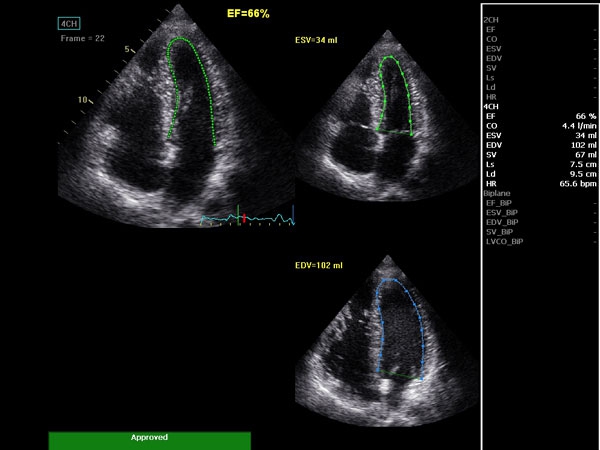

• AutoEF (Auto Ejection Fraction) — функция автоматической недоплеровской количественной оценки глобальной сократительной функции левого желудочка с выделением зоны интереса по технологии спекл-трекинга.

• AFI (Automated Function Imaging) — автоматическое отображение функции ЛЖ — функция позволяет производить качественную и количественную недоплеровскую оценку региональной сократительной функции левого желудочка.